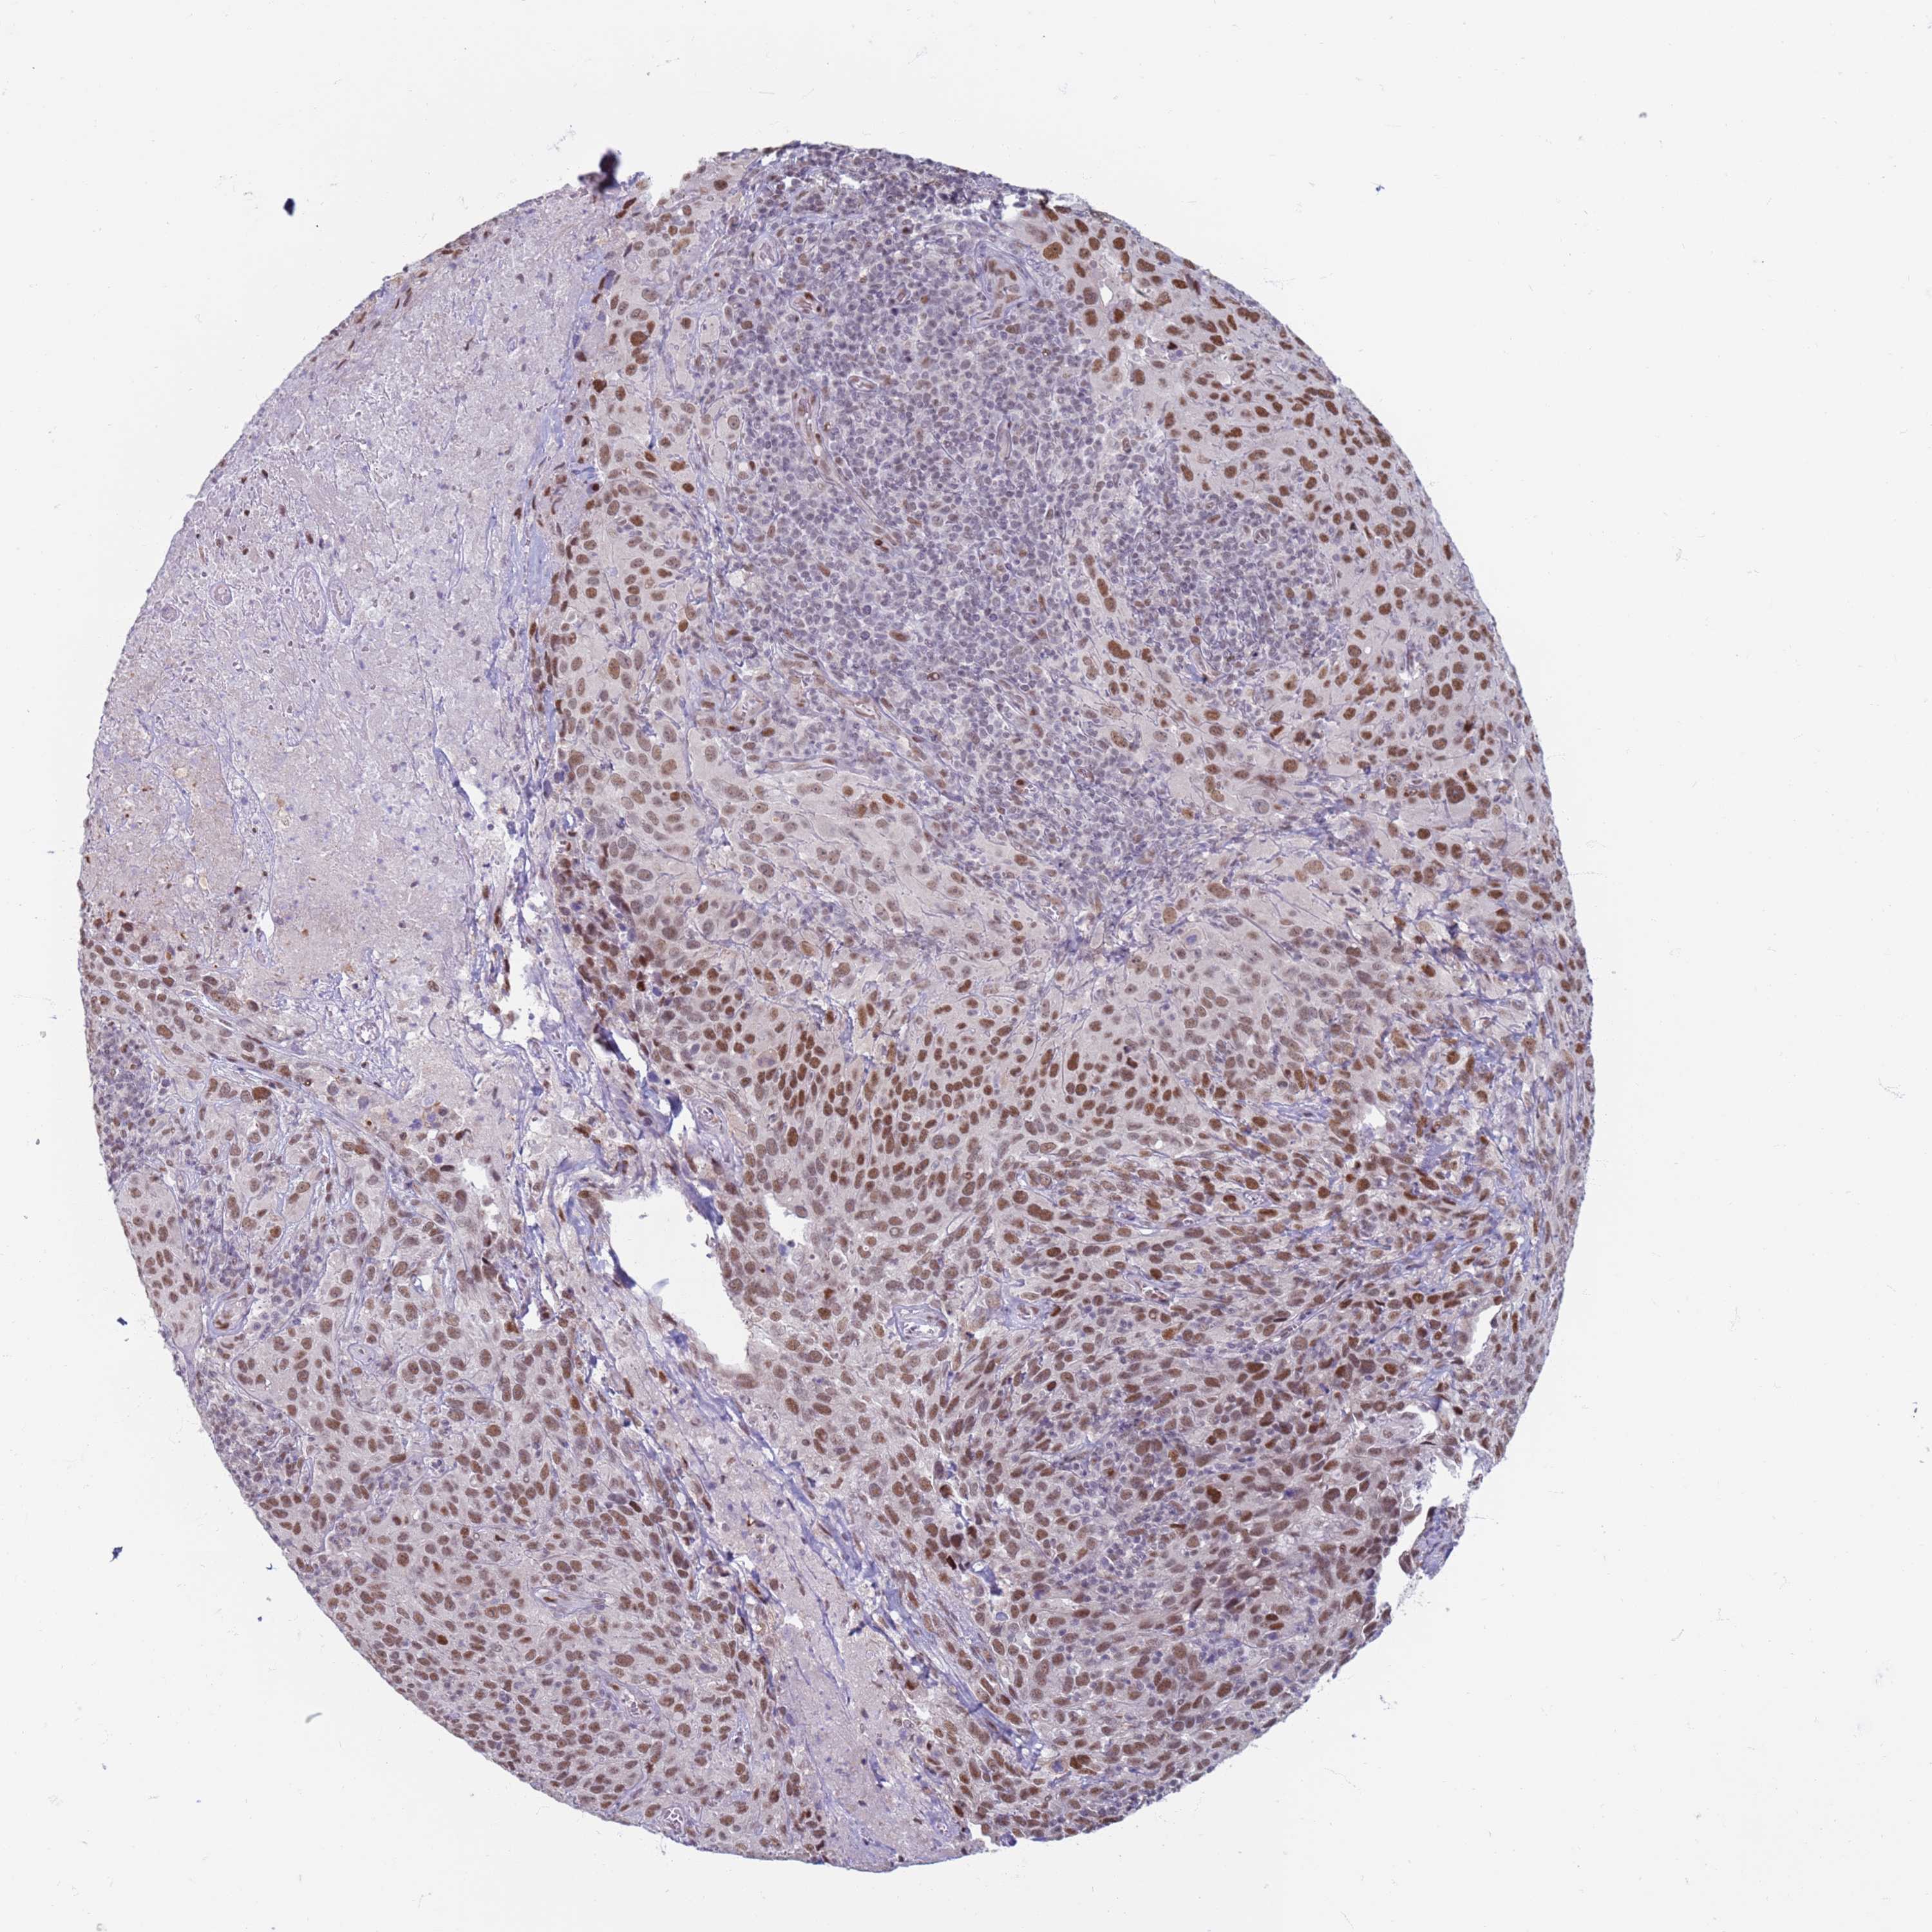

CERVICAL CANCER - Protein expressioni

A mouse-over function shows sample information and annotation data. Click on an image to view it in a full screen mode. Samples can be filtered based on level of antibody staining by selecting one or several of the following categories: high, medium, low and not detected. The assay and annotation is described here.

Note that samples used for immunohistochemistry by the Human Protein Atlas do not correspond to samples in the TCGA dataset.

Antibody stainingi

Antibody staining in the annotated cell types in the current human tissue is reported as not detected, low, medium, or high, based on conventional immunohistochemistry profiling in selected tissues. This score is based on the combination of the staining intensity and fraction of stained cells.

Each image is clickable and will lead to virtual microscopy that enables deeper exploration of all samples and also displays staining intensity scores, fraction scores and subcellular localization as well as patient and tissue information for each sample.

Antibody HPA041906

Antibody HPA043552

Staining

High

Medium

Low

Not detected

Intensity

Strong

Moderate

Weak

Negative

Quantity

>75%

75%-25%

<25%

None

Location

Nuclear

Cytoplasmic/membranous

Cytoplasmic/membranous,nuclear

Squamous cell carcinoma, NOS

Adenocarcinoma, NOS